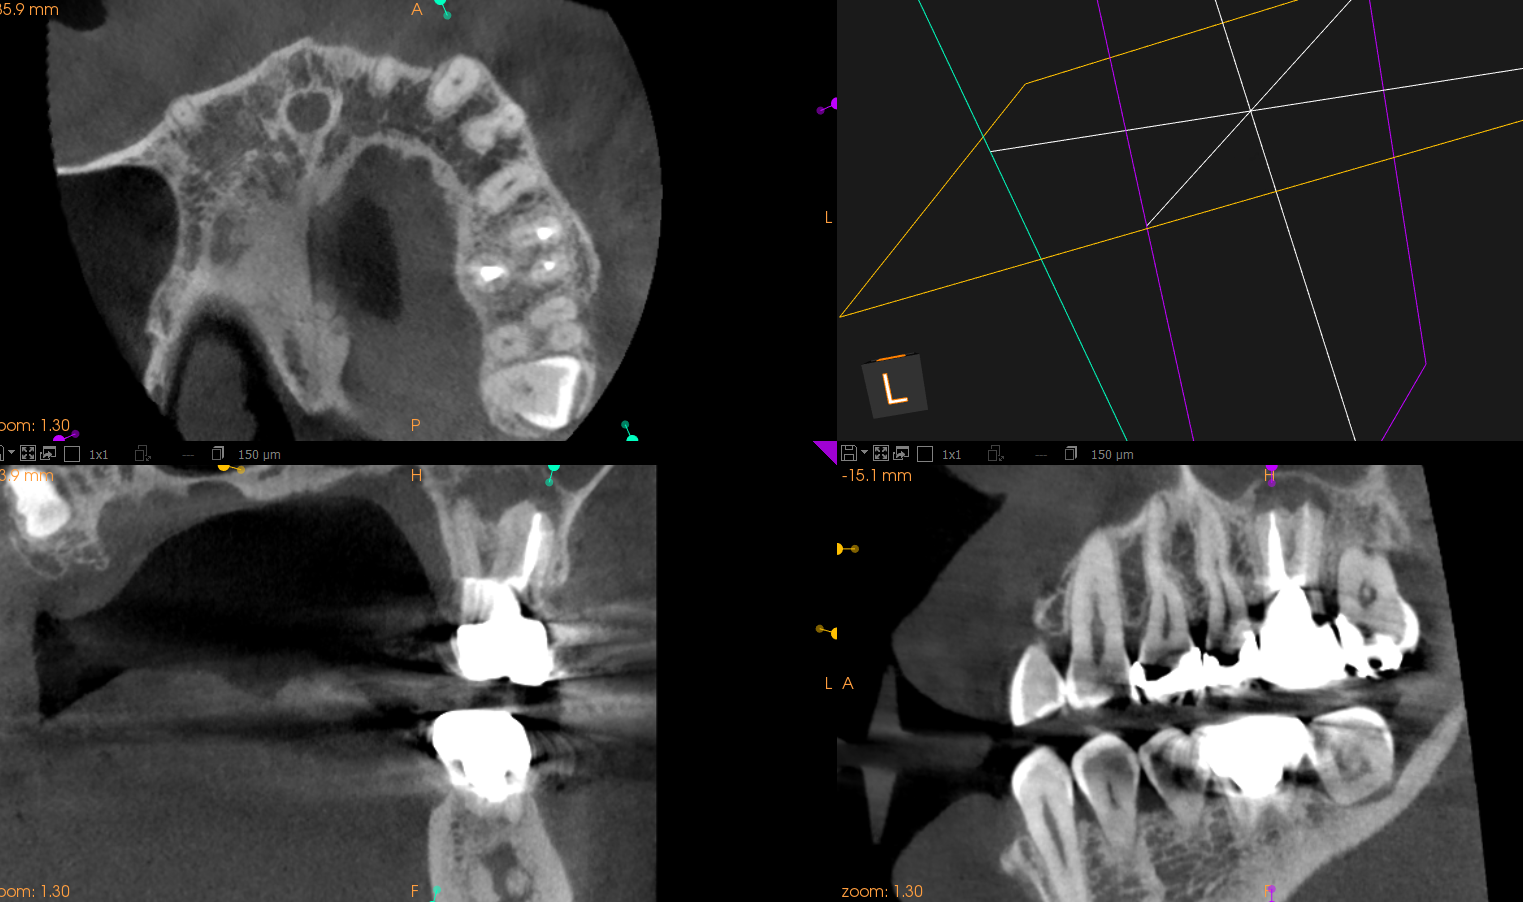

#14 Re-RCT 1yr recall(2024.6.10)

1年前よりも状況がひどくなる。

そこで、Apicoectomyを行うのだが、

MB,DB,Pの3根同時の根切が必要であったので、

Flapを開けてMB,DBを短く切断してその上でIntentional Replantationを行うと言う治療計画にした。

すると1回法で終了するからだ。

#14 MB,DB Apicoectomy→Intentional Replantation(2024.6.21)